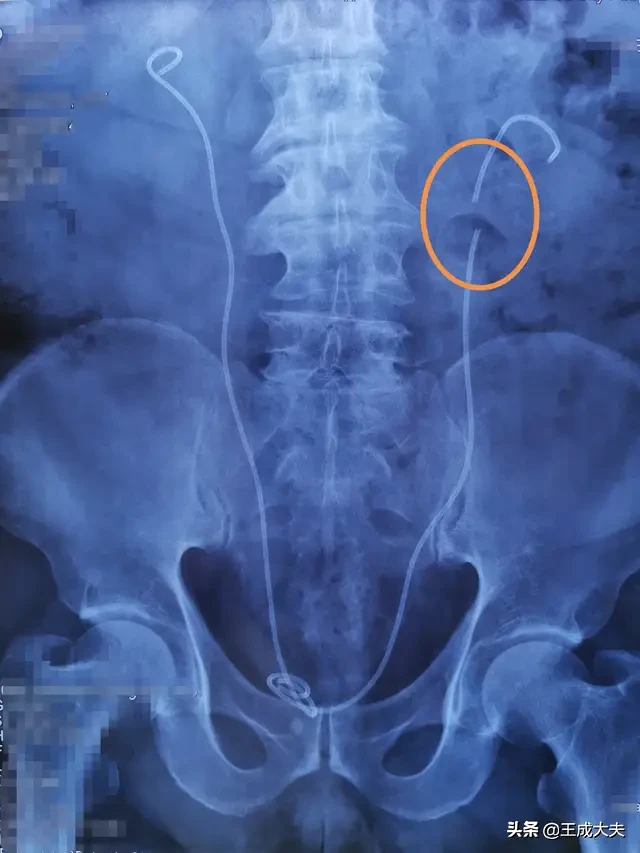

文章插图

体内输尿管支架管保质期3月 , 患者放置近2年 , 导致支架管断裂